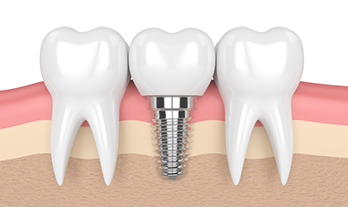

Everything You Need to Know About Dental Implants - Care32 Nashik

Dental implants have revolutionized tooth replacement, offering a durable, natural-looking soluti...

Dental Implant Clinic Near College Road Nashik – Care 32

Looking for a reliable dental implant clinic near College Road Nashik? Discover ...

Dental Implants near Gangapur Road Nashik | Care 32 Dental and Implant Centre

Looking for a trusted dental implant clinic near Gangapur Road Nashik? Discover ...